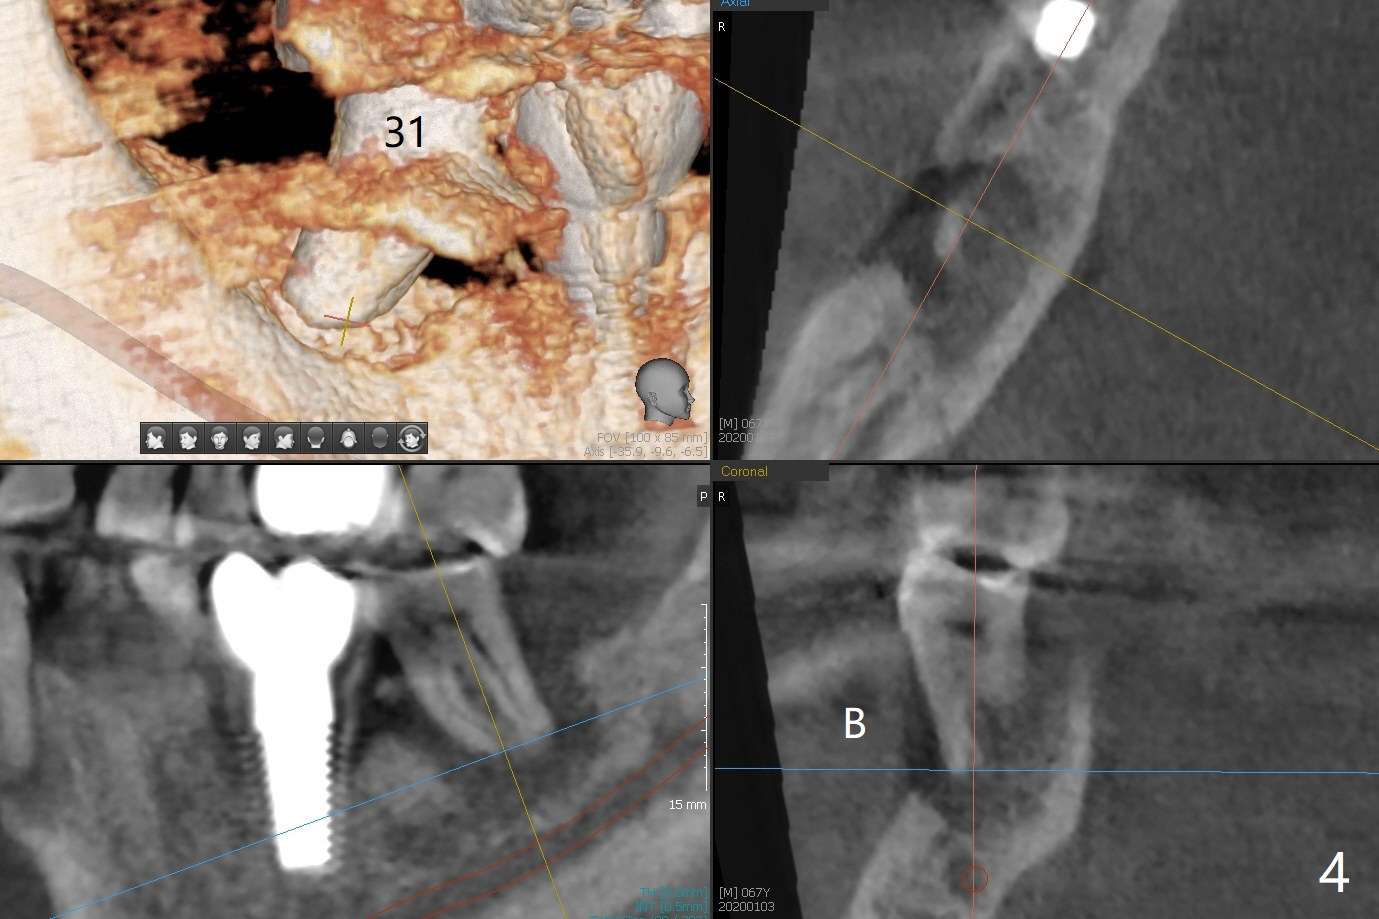

A 67-year-old man returns for periodic exam and #19 impression (Fig.3), which is impossible because there is open bite on the left (Fig.1 *). The latter is related to several periodontal abscesses (supraeruption, Fig.1,2). His chief complaint is mobility of #31 (Fig.3,4). Due to severity of infection, #31 is extracted with bone graft retained by Titanium-Reinforced Membrane (Cytoplast, Fig.5 T). PTFE suture is used. It is easy to tie knots with this non-resorbable (absorbable) suture. The Titanium-Reinforced Membrane exposes 1.5 months postop (Fig.6), which makes its removal easy (Fig.7). In fact the patient is pre-diabetic.